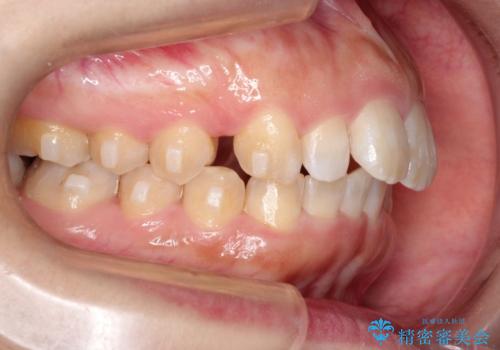

【出っ歯が気になる】インビザライン症例

- 前歯の歯並びの改善を希望され来院された患者様です。

初診時の歯並びの状態としては、上の前歯が下に対して前に飛び出た上顎前突という状態で、前歯は大きく前に飛び出した状態により患者様も口の閉じづらさを感じているとのことでした。また上顎に軽度の叢生(ガタガタ)がありました。

抜歯は行わず上顎の奥のスペースを利用して歯をスライドする方法の他に歯列弓の拡大やディスキング(歯と歯の間の隙間を作る処置)を行い叢生を改善しました。

奥歯を後ろに送る工程では上下でゴムかけをしていただきました。

矯正装置としてはマウスピースを使用しています。

見た目、嚙み合わせ及び、治療期間や施術内容に大変ご満足いただきました。